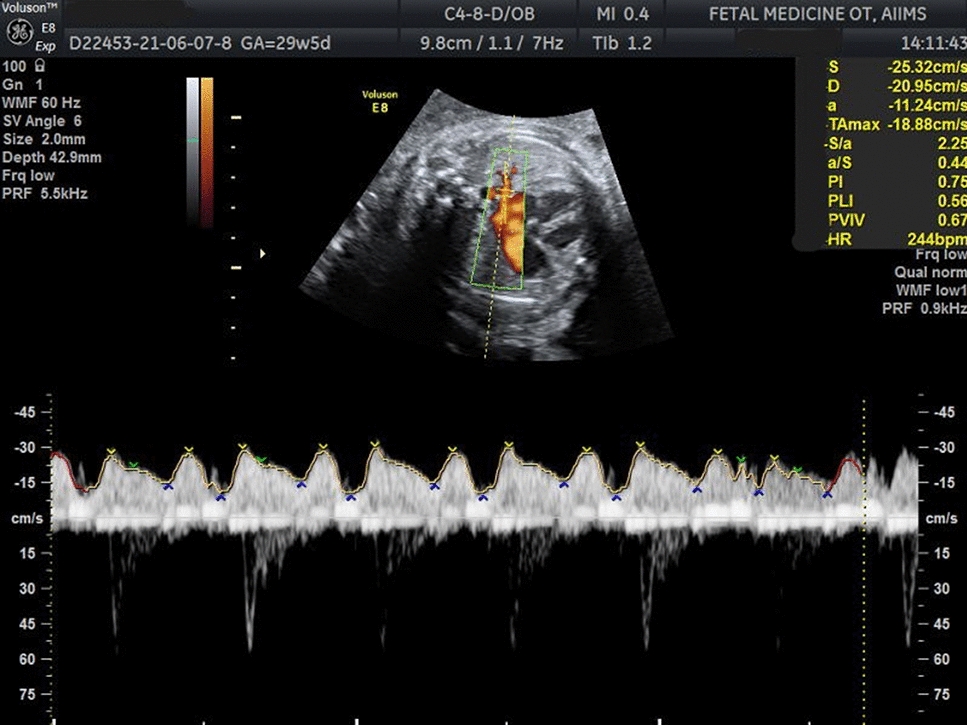

Mean age of the patients was 32.25 ± 6.107 years, and mean BMI was 23.9 ± 3.36 kg/m2. 47.2% had taken medical treatment for a period of 5.9 ± 11.7 months. Regarding parity, 75.4% were nulliparous, and 40.8% patients had infertility as co-existing complaint. According to #ENZIAN, the left ovarian involvement was observed in 67.4% and bilateral involvement noted in 46.1%. A (rectovaginal vagina and septum) was involved in 61% cases, B (uterosacral ligaments and pelvic wall) 63.58% on left and 60.33% on right and C (rectum and sigmoid colon) 33.1% cases.